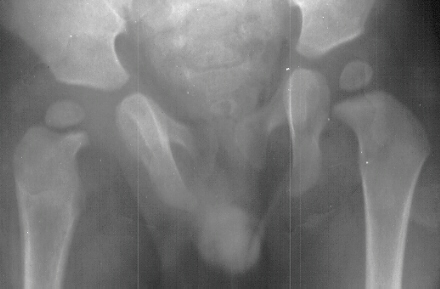

- Post Operative Day 18: R hip Xray: subluxation of R hip, possible metaphyseal

lucency consistent with osteomyelitis. Taken to OR for repeat I & D

of R hip via posterior approach with Penrose drains and hip spica cast

(15cc seropurulent fluid drained). Antibiotics changed to Oxacillin 225mg

IV q4.

Institute. Initial labs: WBC 15,100, ESR 72. R hip Xray: changes in proximal

. metaphysis including lucency and demineralization, hip subluxated. Treated

with oxacillin and Pavlik harness.

- 2 month Office Follow Up: Rt hip Xray: progressive destruction of capital

femoral epiphysis, cystic changes in metaphysis consistent with AVN.

This case is an example of untreated septic arthritis which caused avascular

necrosis of the proximal femur. The primary cause of this is undrained

septic hip. Repeated aspiration is not adequect treatment of a septic hip.